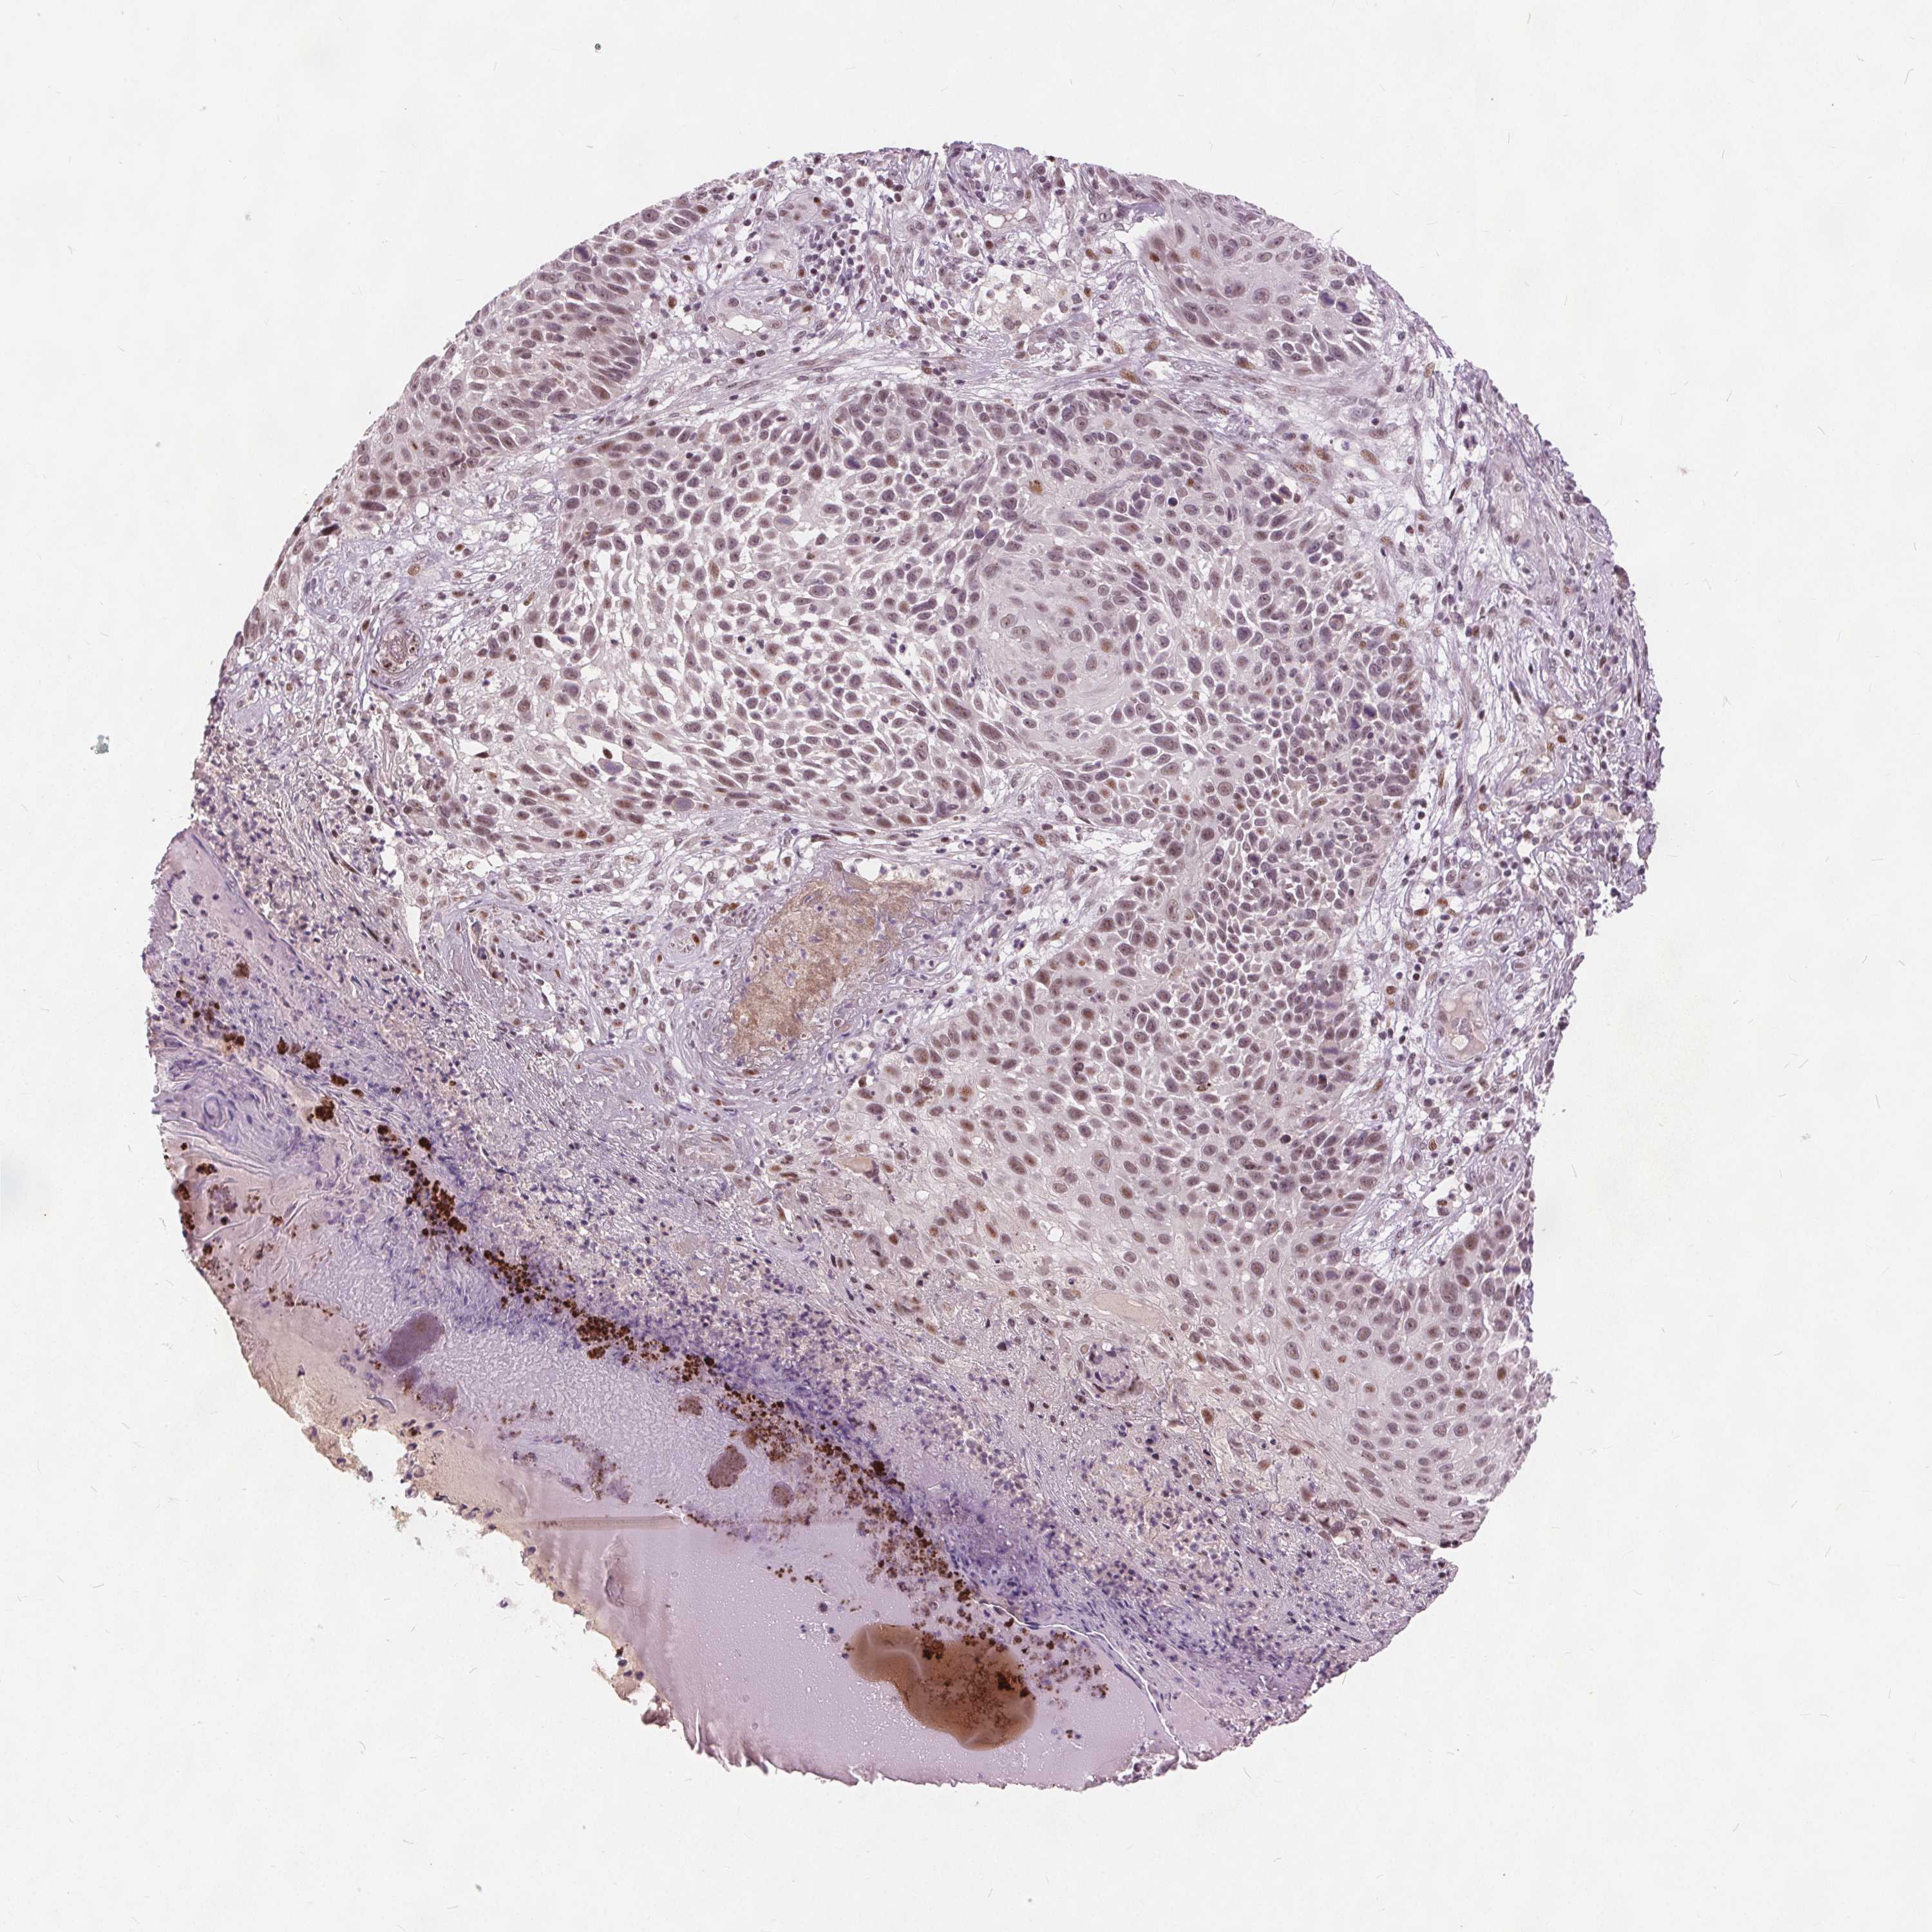

Basal cell and squamous cell cancer

SKIN CANCER - Protein expressioni

A mouse-over function shows sample information and annotation data. Click on an image to view it in a full screen mode. Samples can be filtered based on level of antibody staining by selecting one or several of the following categories: high, medium, low and not detected. The assay and annotation is described here.

Each image is clickable and will lead to virtual microscopy that enables deeper exploration of all samples and also displays staining intensity scores, fraction scores and subcellular localization as well as patient and tissue information for each sample.

Antibody HPA066832

Staining

High

Medium

Low

Not detected

Intensity

Strong

Moderate

Weak

Negative

Quantity

>75%

75%-25%

<25%

None

Location

Nuclear

Cytoplasmic/membranous

Cytoplasmic/membranous,nuclear

Basal cell carcinoma

Squamous cell carcinoma, NOS